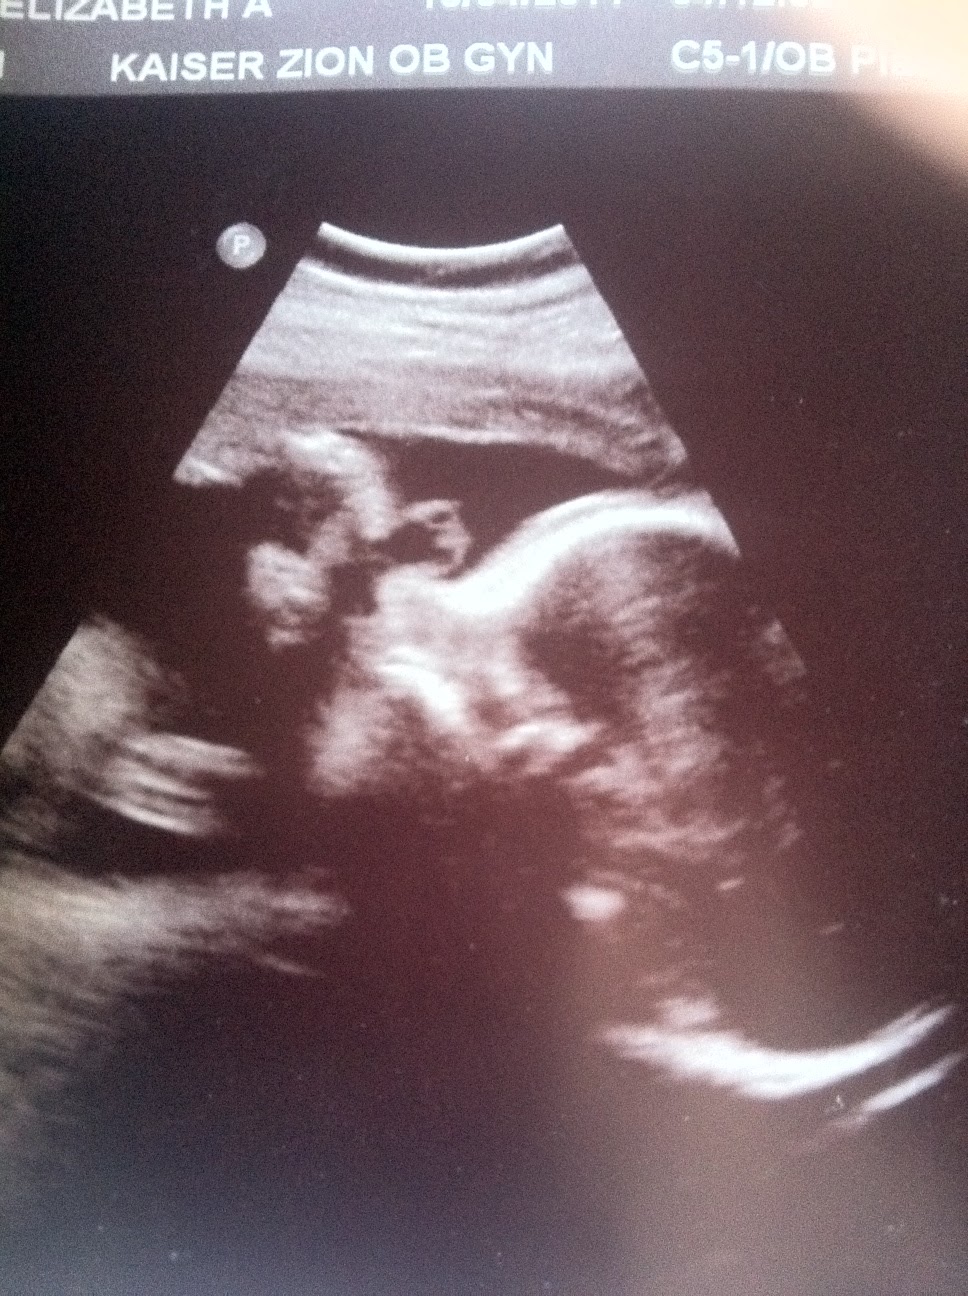

I had a 32 week ultrasound on 10/4 with a different OB (thank god). She was so calm and professional explaining what she had found. The LLD is still there but the ratio is still the same. His right leg is 5cm long (50% for growth that matches the rest of his body) and his left tibia and fibula are 4cm (5% for growth.) The percentiles are kinda scary. But the good news is that his leg did grow and the LLD did not get more significant over the past 4 weeks! She is also very skeptical over the "6th toe" the previous OB pointed out. It isn't a polydactyly toe. She thinks it is either a shiny spot on the ultrasound or possibly some calcification on the side of the foot (maybe an extra bone). Then OB finally noted that "I am not an orthopedist and cannot tell you what treatment would be like. All I can do is mark his growth." She did praised the orthopedist I am seeing on the 18th and said she took her daughter to him when she was having a spinal problem. I'm still not convinced he can properly treat clubfoot with an LLD but at least I'm not completely wasting my time. So I'm marking this week with a little sigh of relief. At least I don't have something new to stress about.

I've attached some pictures of the last ultrasound. The foot/leg pictures are of his clubfoot side. See what you think of the "6th toe"; its the shiny line on the outside of the foot. Then of course I had to add a profile of my rad little dude.